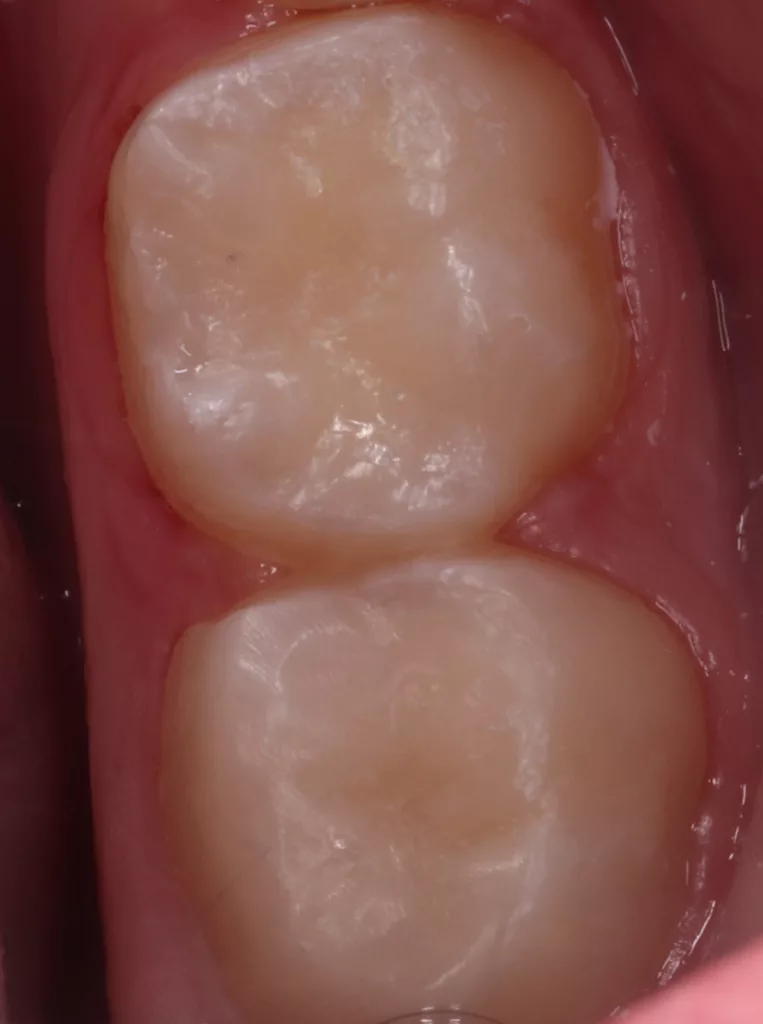

Unter Lokalanästhesie mit dem STA-System (Milestone Scientific, USA) und Septanest 1/200 000 (Septodont, Frankreich) wurde die überstehende Gingiva mit dem Khors Koagulator (Эctatex, Ukraine) koaguliert und der Bereich unter Kofferdam kontaminationsfrei dargestellt (Klammer U67, KSK Dentech, Japan). Die schmalen Fissuren wurden mit dem Fissurenbohrer CD-53F (Mani, Japan) erweitert, um anschließend mittels RONDOflex plus 360 (KaVo Dental, Deutschland) und Pulver 27 µm vollständig gereinigt werden zu können. Es konnte weder durch visuelle Inspektion noch Sondierung mit 0.08 H-file (Mani, Japan) ein Defekt des Zahnschmelzes festgestellt werden. Unter Berücksichtigung der Integrität des Zahnschmelzes, der Symptomlosigkeit, des Behandlungszeitpunktes, Alters des Kindes und Wachstums der Zahnwurzeln fiel gemeinsam mit den Eltern die Wahl auf eine konservative Therapie. Es wurde eine Fissurenversiegelung mit Clinpro Sealant (3M, USA) unter Anwendung eines adhäsiven Behandlungsprotokolls mit Optibond FL (Kerr, USA) durchgeführt. Dieser klinische Fall ist dahingehend einzigartig, da alle anderen ersten und zweiten Molaren des Kindes ebenso von einer PEIR betroffen waren (Grad 1 bis 2 der Läsion nach Seow) (Abb. 3 und 12). Normallerweise ist nur ein Zahn bei einer Patientin oder einem Patienten betroffen. Die Zahnkronen der anderen betroffenen Zähne erwiesen sich bei der klinischen Untersuchung als intakt; die radioluzenten Läsionen innerhalb des koronalen Dentingewebes waren wesentlich kleiner als die von Zahn 36. Daher wurde auch bei diesen Molaren das gleiche Behandlungsprotokoll angewendet und nur eine Fissurenversiegelung durchgeführt.

Im Rahmen der jährlichen Kontrolluntersuchung wurde bei einem achtjährigen Mädchen auf der routinemäßig angefertigten Röntgenaufnahme eine mittelgroße PEIR des Zahnes 46 (Grad 2 der Läsion nach Seow) entdeckt (Abb. 43). Die Patientin war komplett beschwerdefrei und der Zahnschmelz des betroffenen Zahnes sah intakt aus (Abb. 44 und 45). Weil auch hier der PEIR-Defekt gräulich durchschimmerte (Abb. 44 und 45) und der Zahn bereits seit einem Jahr durchgebrochen war, entschieden wir uns in diesem Fall, den Defekt klassisch mit Komposit zu restaurieren. Unter Lokalanästhesie mit Septanest 1/100 000 (Septodont, Frankreich) wurde zunächst Kofferdam mithilfe der Klammer U67 (KSK Dentech, Japan) gelegt (Abb. 45). Weder visuell noch mittels Sondierung konnte eine Verbindung zur Läsion festgestellt werden. Deswegen wurde an der Stelle, an welcher der PEIR-Defekt gräulich schimmerte, intakter Zahnschmelz der lingualen Querfissur entfernt (Abb. 46). Innerhalb der Läsion wurde nekrotisches intrakoronales Weichgewebe vorgefunden (Abb. 47), das problemlos mittels RONDOflex plus 360 (KaVo Dental, Deutschland) mit dem 27-µm-Pulver vollständig entfernt werden konnte. Der Boden des Defektes zeigte eine glatte, runde Form sowie helles, hartes und intaktes Dentin. Eine Präparation war nicht erforderlich, es wurde lediglich die Zahnschmelzkante geglättet (Abb. 48). Für die Restauration kamen erneut das Adhäsiv Optibond FL (Kerr, USA) und das Komposit Estelite ASTERIA OCE, A2B und Universal Flow AO2 (Tokuyama, Japan) zur Anwendung (Abb. 49). 6 Monate nach der Behandlung zeigte sich das Ergebnis sowohl aus klinischer als auch radiologischer Sicht stabil wie die Abbildungen 50 und 51 zeigen.